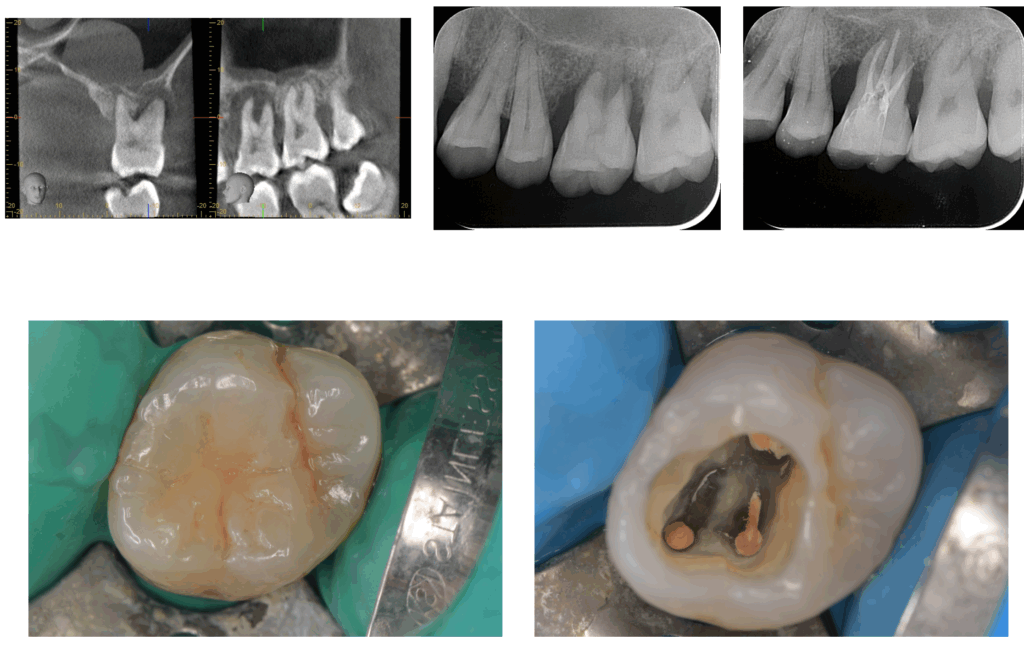

レントゲンでは、歯の根の先端と側面に黒い影(骨の吸収像)が広がっており、

歯を支える骨が一部失われていることが確認されました。

歯周ポケットも7mmと深く、歯周病と根の感染の両方が関与している状態でした。

CTを撮影すると、歯の根の先端だけでなく、根の側面にも感染が波及していました。

古い根管充填材を丁寧に除去し、マイクロスコープで拡大観察しながら

根の奥に残された細菌や汚染物質を徹底的に清掃しました。

数週間後、歯ぐきの腫れは完全に消失し、歯周ポケットも7mm→3mmまで改善。

レントゲンでも、失われていた骨の一部が再生し始めていることが確認できました。